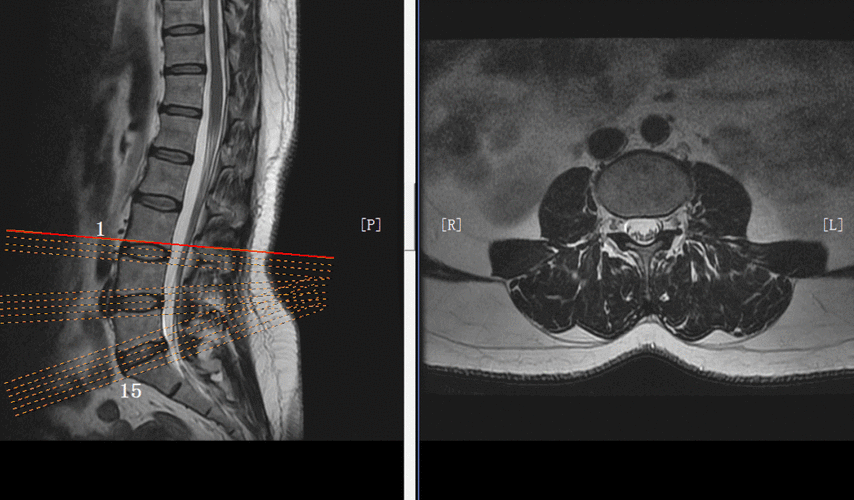

颈椎病的mri诊断技巧